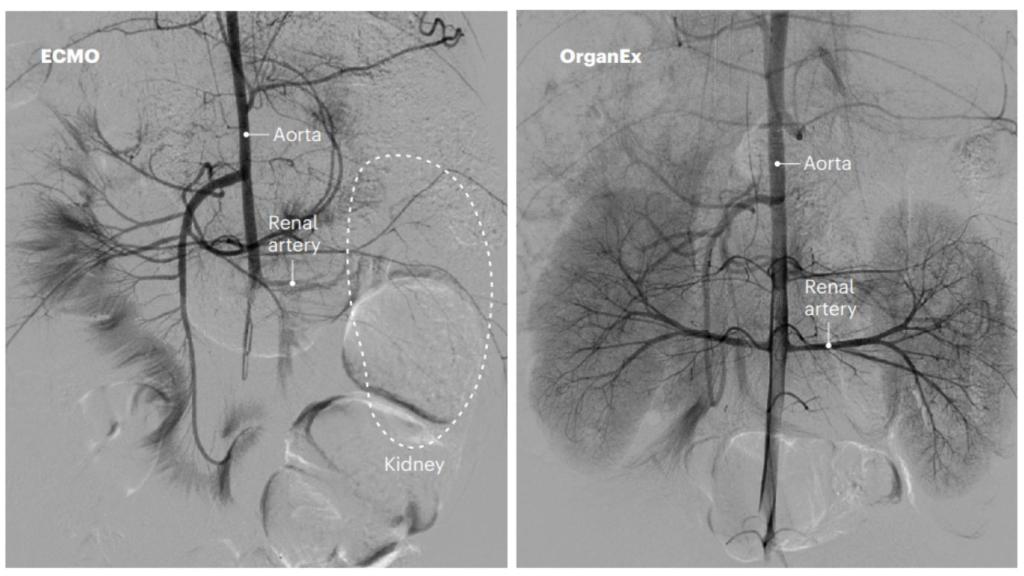

La recuperación postmortem de los riñones de cerdo mediante ECMO (izquierda) y mediante OrganEx (derecha).

En el caso de los cuerpos de los cerdos tratados con ECMO, la perfusión durante seis horas fue incapaz de reanimar a los órganos: la gran mayoría de las venas colapsaron y dejaron de irrigar eficazmente. Los organismos tratados con OrganEx, sin embargo, lograron una revascularización completa con un consumo de oxígeno estable. El análisis de los riñones, hígado, páncreas, cerebro, pulmones y corazón así recuperados reveló una menor destrucción de tejido a nivel celular, y mayores evidencias de que las células volvían a proliferar y estaban reparando los daños.